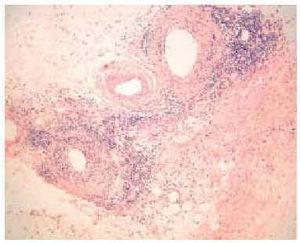

En septiembre de 1999 presentó un nuevo brote de lesiones cutáneas clásicas de dermatomiositis, así como 5 lesiones nodulares en ambos miembros superiores, de unos 3 cm de diámetro, dolorosas, induradas, de superficie poiquilodérmica, sin sintomatología muscular ni elevación de las enzimas musculares. Se realizó una biopsia cutánea de un nódulo del brazo que puso de manifiesto una degeneración vacuolar focal de la capa basal epidérmica y un leve infiltrado inflamatorio linfohistiocitario perivascular en la dermis. Lo más llamativo fue la presencia de una paniculitis de predominio lobulillar con linfocitos, histiocitos y células plasmáticas (fig. 2). En algunas zonas los linfocitos formaban acumulaciones donde se insinuaba un centro germinal (fig. 3) y en otras infiltraban la pared de los vasos (fig. 4).

Fig. 4.--Infiltración linfocitaria de la pared de los vasos. (Hematoxilina-eosina, x100.)